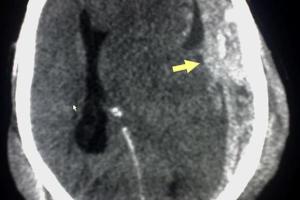

Tratamiento del hematoma subdural crónico